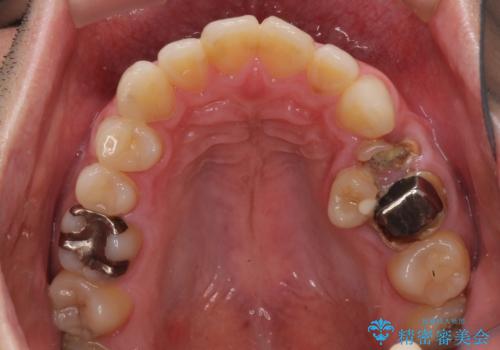

内側に転位した歯とボロボロのむし歯 インビザラインによる矯正治療とむし歯治療

- ボロボロのむし歯とデコボコの歯列を気にして来院された患者様です。

ボロボロとなっていた歯は抜歯が必要な状態でしたが、舌側転位している歯を移動させることで抜歯スペースを埋めることができるため、矯正治療により歯列を整えることとしました。

舌側転位の改善にインビザラインを用いるのはやや難易度が高くなりますが、前歯部のデコボコは軽度であったため、インビザラインによる矯正治療を行うこととしました。

矯正治療後には抜歯が必要な歯に隣接してむし歯となっていた歯をオールセラミッククラウンにて補綴治療を行うこととしました。